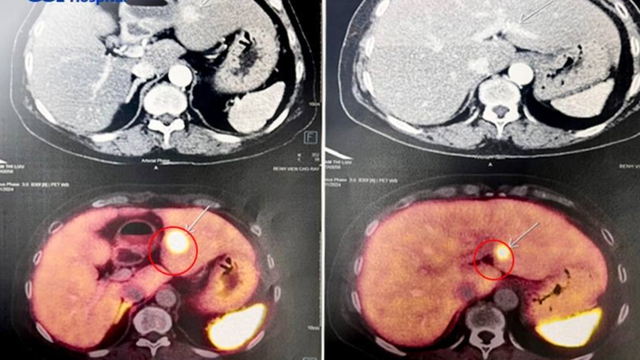

Hình ảnh chẩn đoán các khối u gan, tụy trên CT scan (ảnh đen trắng) và trên DSA là u tuyến nội tiết (màu vàng). Ảnh: BVCC

Bất ngờ, kết quả chụp CT Scan toàn thân cho thấy 6 khối u rải rác khắp cơ thể, gồm 2 khối u tuyến cận giáp hai bên, kích thước 1,2cm và 1,7cm; 1 khối u ở vú phải; một ở gan và 2 u ở tụy. Kết quả chụp mạch máu số hóa xóa nền (DSA) và siêu âm nội soi, bấm sinh thiết, xác định u ở gan và tụy là u thần kinh nội tiết.